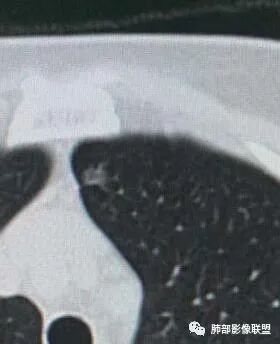

二.左肺上叶前段磨玻璃结节:

该结节较大,边界清楚,小叶间隔阻挡特征相当明显,微浸润腺癌的诊断几乎没有争议!